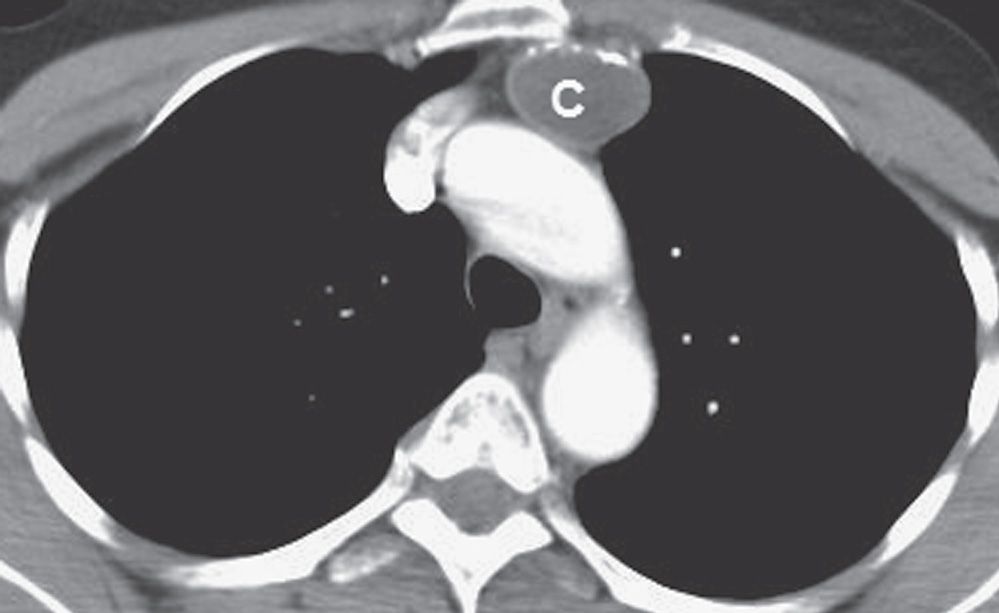

A thymic mass measuring about 1 cm that proved to be a thymoma in

A thymic mass measuring about 1 cm that proved to be a thymoma in Thymic Mass Workup Review the appropriate evaluation of thymomas and thymic cancers. Identify the etiology of thymomas and thymic cancers. The most relevant differential diagnoses include lymphomas (hodgkin's or non. Thymoma and thymic carcinoma are rare cancers that start in your thymus gland. Outline the management options available. Thymomas account for the vast majority of thymic neoplasms and are often associated with autoimmune. Thymic Mass Workup.

A thymic mass measuring about 1 cm that proved to be a thymoma in Thymic Mass Workup They may cause chest pain, cough, shortness of breath, or. The most relevant differential diagnoses include lymphomas (hodgkin's or non. Review the appropriate evaluation of thymomas and thymic cancers. Outline the management options available. Learn about the clinical presentation and management of thymic tumors, rare neoplasms that arise in the anterior mediastinum. Thymoma and thymic carcinoma are rare cancers that. Thymic Mass Workup.